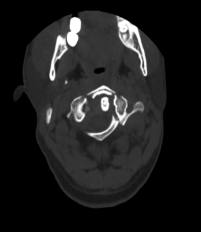

该患者的治疗关键在于两个方面:一是能否将螺钉置入漂浮的寰椎侧块中从而达到骨折的复位及固定?二是该患者同时还伴有双侧枢椎椎弓根先天性发育不良、椎动脉高跨,能否顺利植入椎弓根螺钉?经过为期一周的颅骨牵引和术前准备,杨先生于近日接受了手术。对于此类颈椎手术,经验丰富的姜为民主任早已开展了多年,与以往不同的是这次手术多了一台“GPS”---“O”-臂机,这也是我院首次术中开机实用。

术中“O”-臂机导航图像

在麻醉手术科的配合下,有了高精尖的第二代“O”-臂机的辅助,加之姜主任丰富的临床经验,手术非常顺利。第二代“O”-臂机扫描颈椎三维重建显示寰椎移位的骨块复位完成,寰枢椎椎弓根螺钉位置良好。术后,患者颈部疼痛症状明显改善。